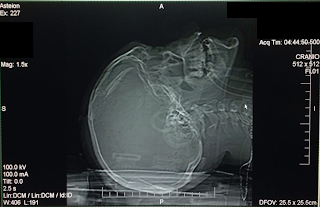

A fratura craniana é a ruptura de um osso do crânio. As fraturas estão presentes na maioria das tomografias de pacientes que sofreram lesões cerebrais. As fraturas cranianas podem lesionar artérias e veias, provocando sangramento nos espaços em torno do tecido cerebral. As fraturas podem romper as meninges – as camadas de tecido que revestem o cérebro. Caso isto aconteça, o líquido cefalorraquidiano, que circula entre o cérebro e as meninges, pode sair pelo nariz ou pelo ouvido.

A fratura craniana com afundamento de crânio é o fragmento ósseo fraturado afundado, comprimindo e lesionando o tecido cerebral adjacente. O fragmento ósseo também pode causar a laceração da dura-máter (membrana que envolve o cérebro) resultando no vazamento do líquido cefalorraquidiano.